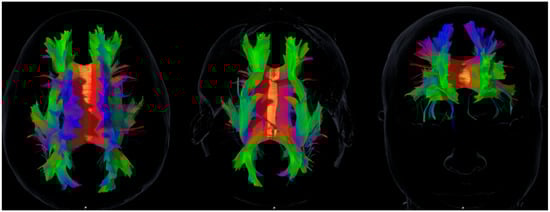

The following association tracts were reconstructed: superior longitudinal fasciculus (SLF), inferior longitudinal fasciculus (ILF), uncinate fasciculus (UF), inferior fronto-occipital fasciculus (IFOF), and cingulum. The superior fronto-occipital fasciculus (SFOF) was also reconstructed. However, given the ongoing controversy about its existence in humans [], SFOF volumes are reported for transparency but not emphasized in the main discussion or interpretation of results. Figure 1 provides an anatomical overview of the reconstructed association tracts included in the correlation analyses, illustrating the structural framework for the cognitive, emotional, and social domains explored.

Figure 1. Representative diffusion tensor imaging (DTI) tractography showing the main association pathways analyzed in this study: superior and inferior longitudinal fasciculi (SLF, ILF), uncinate fasciculus (UF), inferior fronto-occipital fasciculus (IFOF), and cingulum. These reconstructions illustrate the anatomical substrates explored in relation to the cognitive, emotional, and social domains assessed. The figure is intended to provide a structural overview and does not imply direct or deterministic tract–function associations. Axial, sagittal, and coronal views are shown in native space for visual orientation.